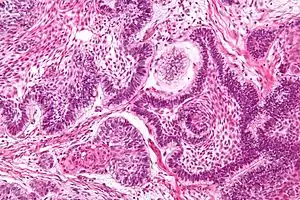

Perivascular pseudorosette

A perivascular pseudorosette consists of a spoke-wheel arrangement of cells with tapered cellular processes radiates around a wall of a centrally placed vessel. The modifier “pseudo” differentiates this pattern from the Homer Wright and Flexner-Wintersteiner rosettes, perhaps because the central structure is not actually formed by the tumor itself, but instead represents a native, non-neoplastic element. Also, some early investigators argued about the definition of a central lumen, choosing “pseudo” to indicate that the hub was not a true lumen but contained structures. Nevertheless, this pattern remains extremely diagnostically useful and the modifier unnecessarily leads to confusion. Perivascular pseudorosettes are encountered in most ependymomas regardless of grade or variant. As such, they are significantly more sensitive for the diagnosis of ependymomas than true ependymal rosettes. Unfortunately, perivascular pseudorosettes are also less specific in that they are also encountered in medulloblastomas, PNETs, central neurocytomas, and less often in glioblastomas, and a rare pediatric tumor, monomorphous pilomyxoid astrocytomas.[2]

Micrograph of perivascular pseudorosettes

Structure of a perivascular pseudorosette